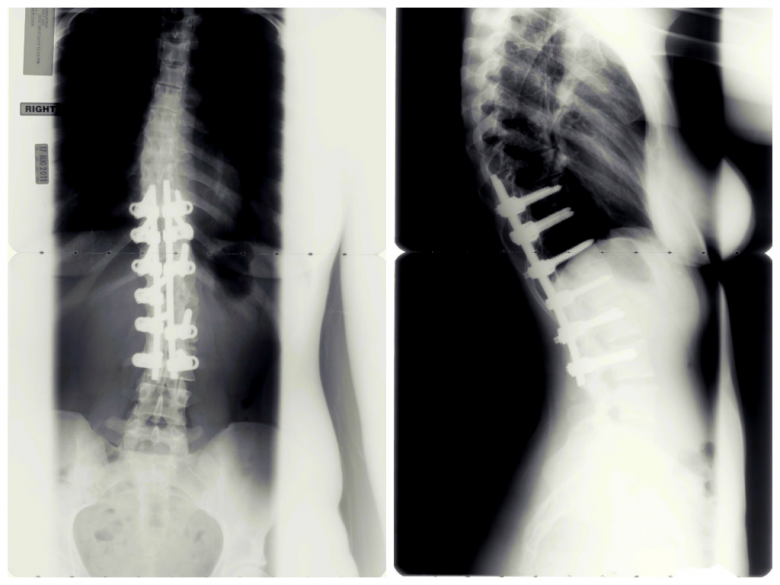

So, over spring break of my freshman year of high school, I had a 6-level spinal fusion from T10-L3. Methodist Hospital is an excellent vacation spot. Basically a combination of metal rods, hooks and screws were attached to my vertebrae to join the bones and straighten them out, and donor bone tissue (both from my own hip and…well, someone who is not me) was used to fuse the whole thing together. This is very similar to the surgery that my sister, Grace, has underwent TWICE.